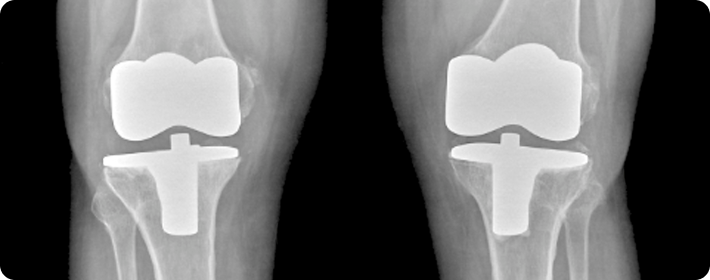

인공관절 수술

손상된 관절을 인공 관절로 교체하는 수술입니다. 전치환술, 부분치환술, 재치환술 등 다양한 방법으로 시행되며 각 관절의 상태에 따라 선택됩니다.